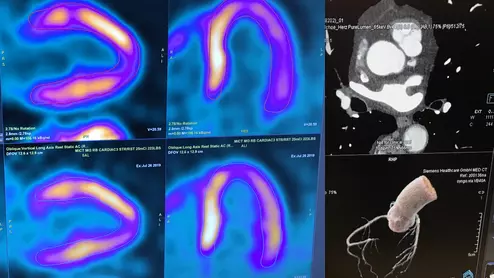

The ASNC is one of several medical imaging societies asking Congress to repeal the appropriate use criteria (AUC) criteria mandate. They say it poses issues for clinicians and is becoming outdated by changes in CMS payment systems. The AUC requirements call for documentation using CVMS authorized software in order to show advanced imaging such as nuclear and CT is justified, or else Medicare payments might be withheld.

American Society of Nuclear Cardiology (ASNC) delegates to the American Medical Association (AMA) House of Delegates 2022 meeting Stephen Bloom, MD, and Nishant Shah, MD, explain a new AMA policy asking Congress to revise its clinician decision support mandate.